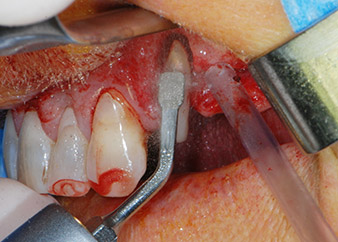

Einen Monat nach dem Eingriff waren sowohl die Schmerzen als auch die Entzündung an Zahn 24 minimal, die Zahnbeweglichkeit lag jedoch noch bei Miller-Klasse 2. Nach Freilegung und Reinigen des infizierten periapikalen und periradikulären Gewebes wurde das Ausmaß des Knochendefizits deutlich (Abb. 2 und 3).

An der bukkalen Wurzel fehlte der gesamte vestibuläre und distale Knochen. Das Attachment beschränkte sich weitgehend auf die palatinale Wurzel, was die anfängliche schlechte Prognose unterstreicht. Auch Zahn 27 wies ein verringertes horizontales Attachment (vgl. Abb. 12) und eine kleine apikale Aufhellung (Abb. 1) auf, allerdings ohne klinische Symptome.

Zunächst wurde in einem Versuch, das Paro-Endo-Problem zu lösen, an der verbleibenden Wurzeloberfläche ein vorsichtiges Debridement mit einem piezochirurgischen Gerät vorgenommen (Piezomed, W&H) (Abb. 4); dann wurde der Apex mit dem gleichen Instrument im Sinne einer WSR abgetragen, um das verbleibende infizierte apikale Gewebe zu entfernen (Abb. 5). Eine retrograde Füllung war nicht notwendig, da die orthograde Füllung gerade revidiert worden war.